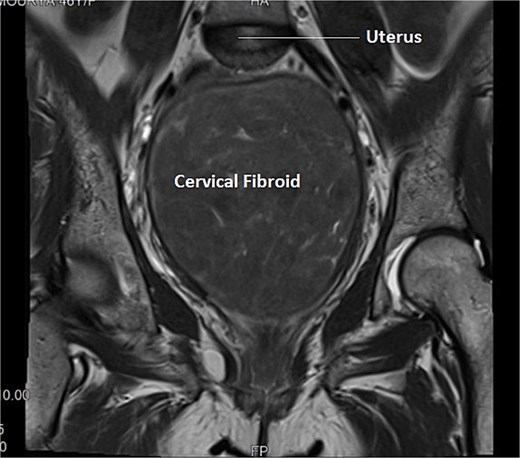

A 46-year-old female, Para 2 Living 2, peri-menopausal, both vaginal deliveries, last childbirth 18 years back, presented to emergency with the incomplete voiding of urine for two days. She was admitted in emergency. She also complaint of pain and abdominal distension for 5–6 months. There was also associated complain of heavy menstrual bleeding for 4–5 months and increased frequency of micturition for 2–3 months. General and systemic examination were normal except for mild pallor. On per abdominal examination, a large globular, firm non-tender mass was felt with well-defined margins and restricted mobility. Size of mass was corresponding to 18–20 weeks gravid uterus. The lower margin of the mass could not be reached. Cervix could not be visualized separately, instead ~8 × 8 cm smooth bulging mass was seen in upper end of vagina. On ultrasonography uterus 10 × 4.7 cm, ET-3 mm, large heterogenous mixed echoic solid mass from cervical portion 16 × 10 cm. Mass was further evaluated with MRI which reported cervical myoma originating from posterior wall ~20 × 9.2 × 17.6 cm displacing the endocervix anteriorly, while the rest of the uterus was displaced antero superiorly. This large well-defined mass occupying whole of cervix and distending the upper vagina, was suggestive of giant cervical leiomyoma, as shown below in Fig. 1. Surgical plan was discussed with the patient and attendants, to which they opted for total abdominal hysterectomy with preservation of bilateral ovaries as her family was completed. After pre-anesthetic workup, the patient was taken up for total abdominal hysterectomy with bilateral ureteric stenting. On opening the abdomen, a giant fibroid of ~20 × 16 cm, was seen occupying the pelvis and abdominal cavity, uterus was sitting on the fibroid, giving the appearance of a Lantern on saint Paul’s dome [6].

Longitudinal section of MRI image of Case 1 – shows uterus sitting on the top of large cervical fibroid, giving the appearance of a lantern on saint Paul’s dome.

Transverse section of MRI of Case 2 – similar multi-sequential transverse sections aids in clear delineation of course of ureter and its relationship with uterine artery in this case of distorted anatomy because of giant cervical fibroid.